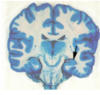

State where this stroke has occured

Right MCA